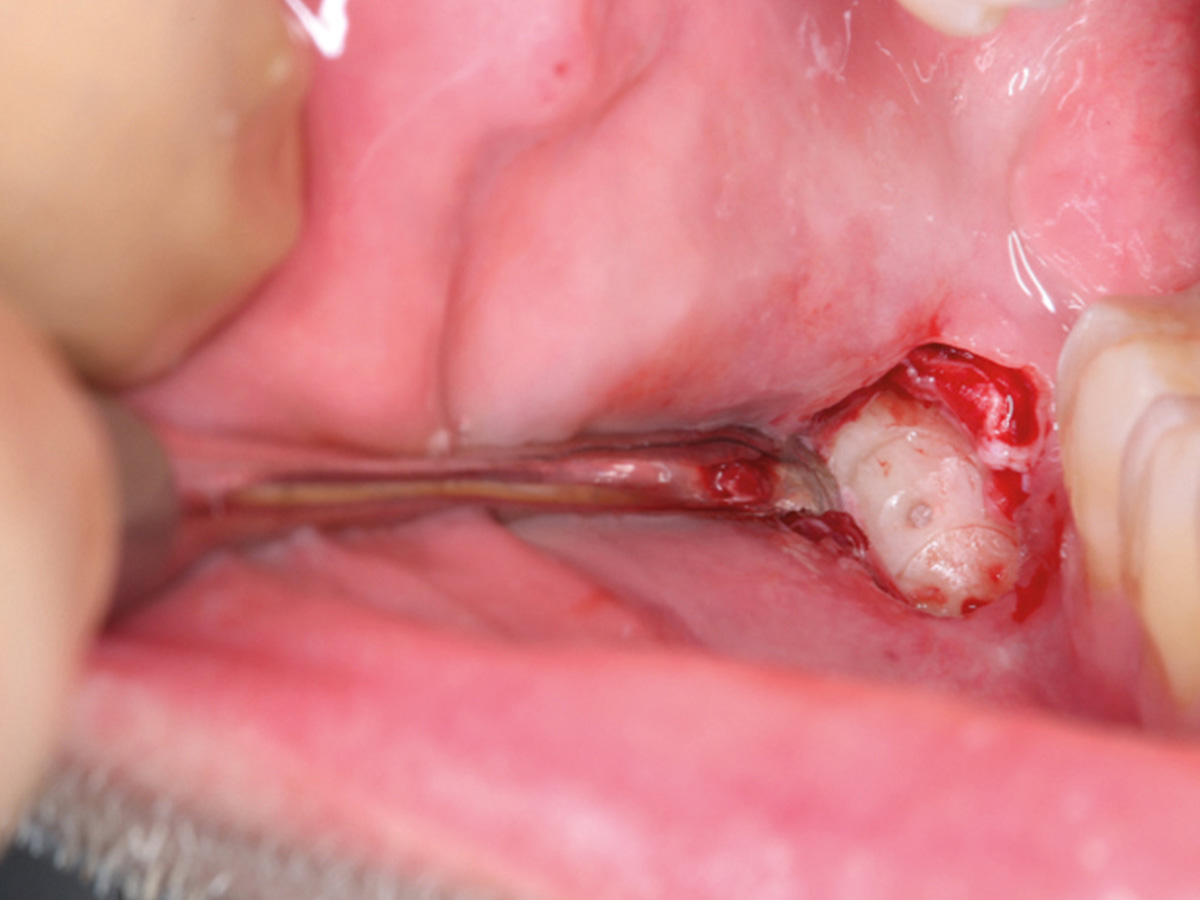

Abbildung 9

Retromolarer Eigenknochengewinn.